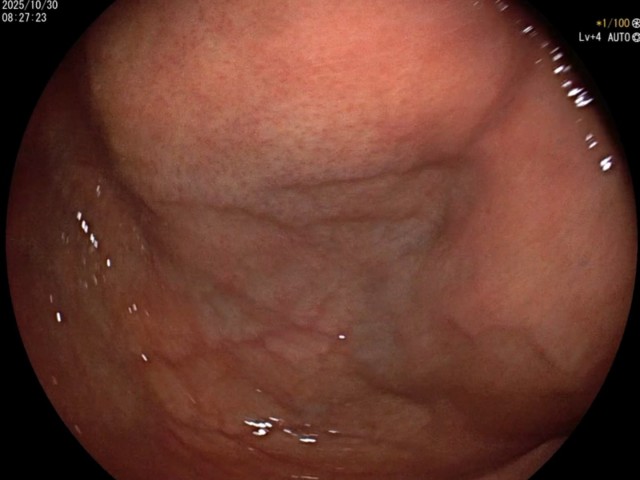

反思 | 赶高铁时一过性晕厥的老年男性

昨天值班遇到的一例晕厥病例,差点漏诊,而最终的解法,始于最简单而质朴的查体。国庆中秋双节的最后一天,8号的早上8点,抢救室床旁晨交班,病人依旧是多而重,交到6床,一个刚入室不久的病人,准备去做CT,夜班医师汇报病史:69岁男性,本次因“头晕伴一过性晕厥1小时”为主诉入抢,1小时前于高铁站因即将赶不上高铁走路快时突发头晕,伴一过性晕厥,约3-4分钟后清醒,清醒后诉今晨未吃早餐,已服用降压药物,仍有头晕头痛、四肢乏力等不适,无胸闷胸痛,无畏寒发热,无咳嗽咳痰,无恶心呕吐,无肢体麻木,无视物模糊等不适,路人拨打120送至我院急诊就诊。既往高血压,长期服用氨氯地平+福辛普利,血压控制一般;糖尿病,长期